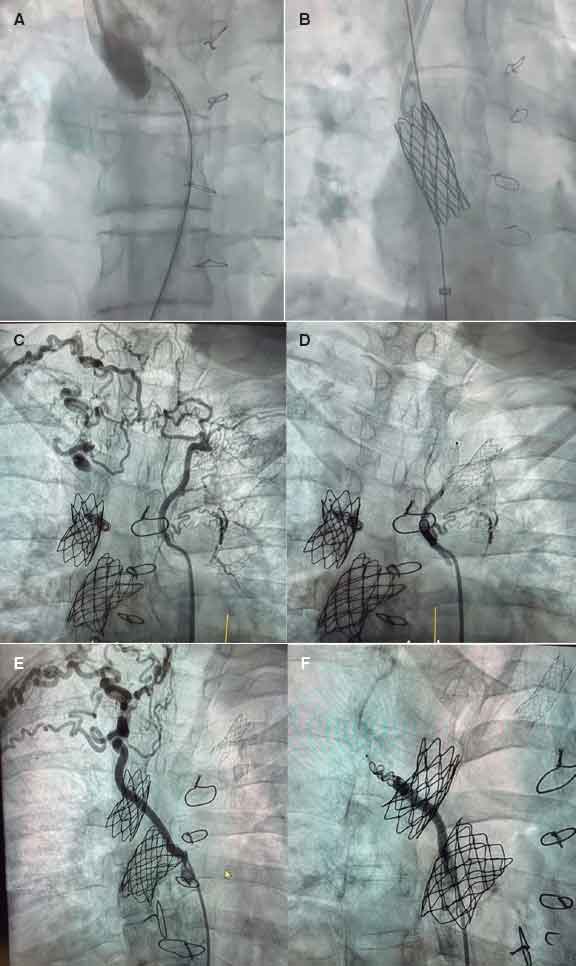

In our setting, the joint work model established since 2015 between pediatric and adult teams illustrates this philosophy. It is not just about sharing a cath lab but generating shared spaces for discussion and decision-making through multidisciplinary clinical sessions to standardize criteria and enable individualized strategy planning. A recent example reflecting the benefits of this collaborative model is a Fontan optimization case involving stenting and collateral closure. The patient was a 41-year-old woman with complex congenital heart disease and single-ventricle physiology—characterized by atrioventricular concordance with ventriculoarterial discordance, complete transposition of the great arteries, a large ventricular septal defect, pulmonary stenosis, and right ventricular hypoplasia—who had undergone multiple surgical procedures (Blalock–Taussig shunt at 13 months, systemic–pulmonary shunt at 2.5 years, bidirectional Glenn at 9 years, and extracardiac Fontan at 17 years). She exhibited reduced functional capacity and Fontan-associated hepatopathy. Cardiac catheterization confirmed a severely calcified Fontan conduit with significant stenosis at its insertion into the right pulmonary artery. Balloon sizing was performed, followed by implantation of a covered stent postdilated with a 20-mm balloon, achieving a good result. A marked stenosis at the Glenn-to–right pulmonary artery anastomosis was confirmed via right internal jugular vein, and a 34 mm bare-metal stent was implanted (figure 1A,B). The aortography performed via arterial access revealed the presence of large aortopulmonary collaterals supplying the 2 upper lung lobes, which were successfully occluded. The first one, toward the right and left upper lobes, was closed using an Amplatzer Vascular Plug 4 (Abbott Cardiovascular, United States) and coils; the second, toward the right upper lobe, was also closed with an Amplatzer Vascular Plug 4 and coils (figure 1C,F). This case illustrates the synergy between pediatric and adult interventional cardiologists in completing treatment.

Figure 1. Fontan optimization. A: stenosis at the Glenn–right pulmonary artery anastomosis. B: bare-metal stent implanted in the stenosis. C: large aortopulmonary collateral supplying the right and left upper lung lobes. D: occlusion of this collateral. E: large aortopulmonary collateral supplying the right upper lobe. F: occlusion of the collateral.